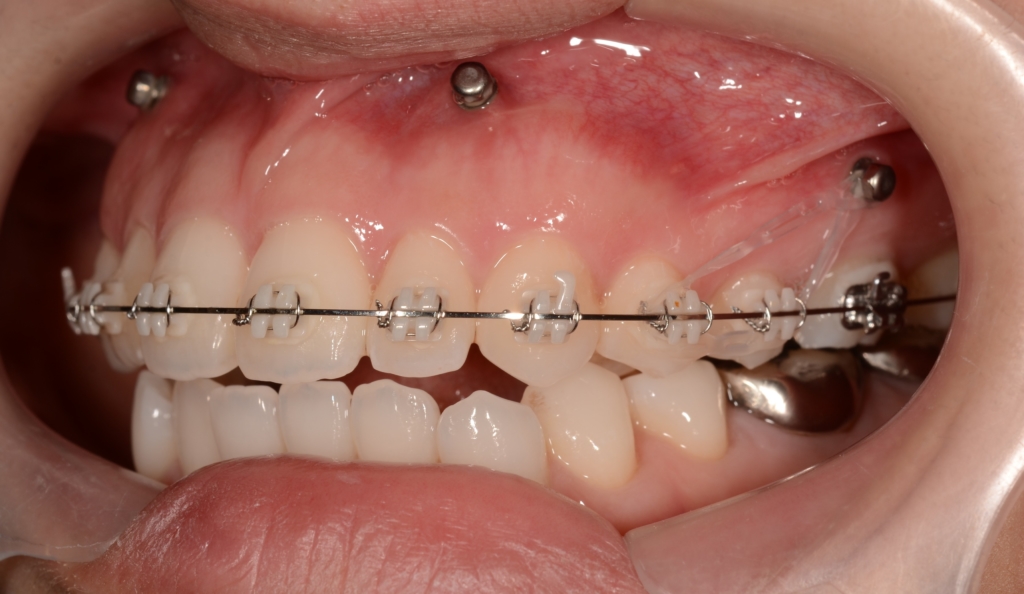

噛み合わせがしっかりしたところで、上下とも第一小臼歯を抜歯して前歯を後方へ最大限に引っ込めて行きます。

当初は最大限に前歯を引っ込めて行く予定だったのですが、治療途中で患者さんから「このくらいで良いかも!?」という状態評価が出てきました。

そこで、その時点からは力を加減して残る隙間を閉じて、噛み合わせを確立するように、治療プランに修正を加えて進めて行きました。